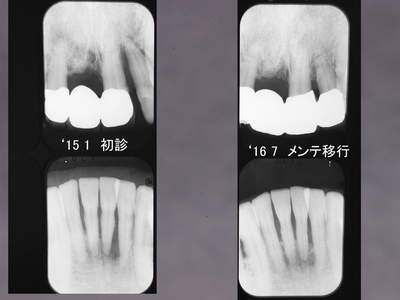

咬合性外傷

左上犬歯近心の骨欠損です。

EPT+.プラークコントロールが非常に良い方で赤染めではほとんどどこも染まりません。

ブラキシズムによる外傷と診断し、スケーリング、ルートプレーニングは一切せずナイトガードと自己暗示療法による外傷のコントロールを試みました。

初診と3ヶ月後の比較です。骨が少しずつ戻ってきました。